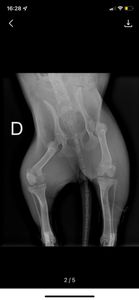

Segundo exames de Raio X, o atropelamento causou 2 fraturas na regiao de pelve e necessita de intervencao cirurgica com custo aproximado em R$3900 reais, que é um custo bastante elevado e precisamos do apoio e da colcaboracao de todos para não deixa-lá morrer, pois ela não consegue se colocar de pé devido a gravidade das fraturas.